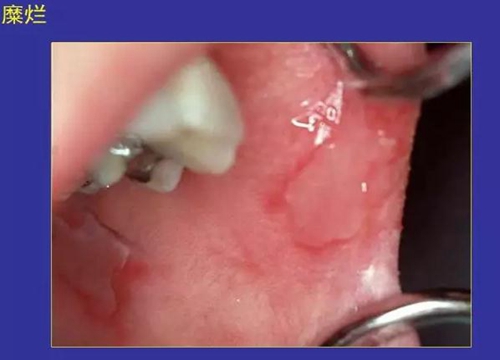

5.糜爛:黏膜表淺缺損,不損及基底細(xì)胞層。

正??谇火つぜ俺R姴p圖